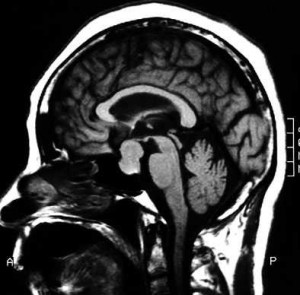

1つは、脳下垂体にACTHといって、コーチゾルの分泌を刺戟するホルモンが、この脳下垂体にできる良性腫瘍によって多量に分泌されるためにコーチゾルが多量にされる”クッシング病”です。2つ目は、脳下垂体以外にできた腫瘍によってACTHが多量に分泌される”異所性ACTH症候群”です。3つ目は、 ACTHには依存しないで、副腎皮質そのものからコーチゾルが多量に分泌されるものです。これらを総称してクッシング症候群と呼ぶのですが、下垂体にできたACTH産生腫瘍の場合に限り”クッシング病”として区別します。これは最初に報告した、アメリカの脳神経外科医ハーヴェイ・ウイリアムス・クッシングの名前に由来します。

下垂体腺腫の場合には、その大きさは様々です。非常に小さい場合にはMRIなどの画像診断だけでは診断が困難なこともあります。私が経験した症例におきましてもマイクロアデノーマと言って最大直径が10mm以下、あるいは2−3mmのものもあります。この場合には、細いカテーテルを下垂体の近くの左右の静脈(海綿静脈洞)に挿入して、左と右のACTHの濃度の差を比較することによってその存在を推定するなどの精密検査を要することがあります。マクロアデノーマ(最大直径が10mm以上)の場合には、下垂体の造影MRIで大体診断が確定いたします。

下垂体腺腫の場合には、最新の治療方として、鼻孔からのアプローチで腫瘍摘出できるため患者さんは大変楽になったと思います。ただし、これもその施設の医師の技術的能力によります。小さい場合には、完治も望めますが大きい場合、特に巨大なものでは、再発も多くその場合には、ガンマナイフやサイバーナイフと言った、定位的放射線治療といったかなり特殊な治療法が必要になります。

<経鼻孔的経蝶骨洞下垂体腺腫摘出術>